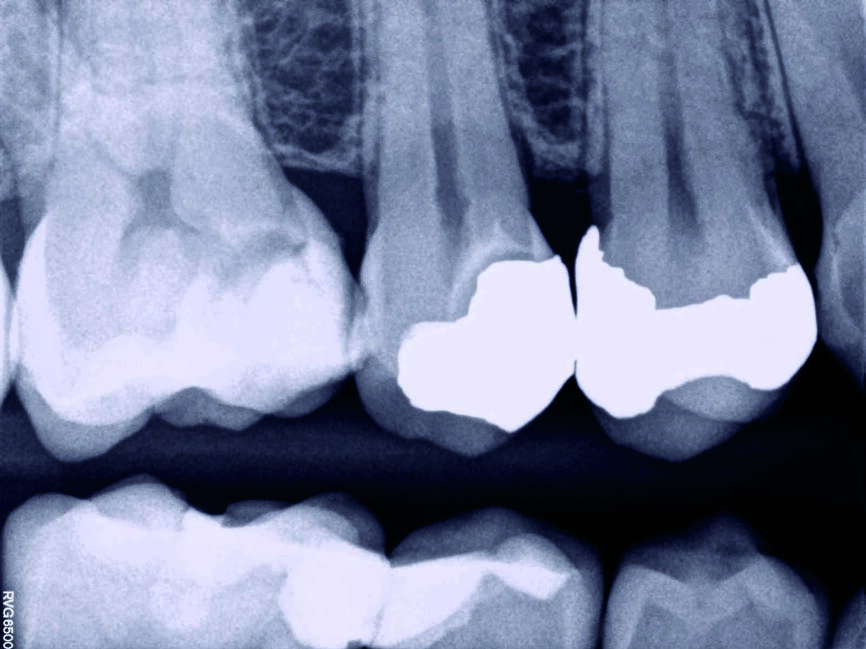

Ein 35-jähriger Patient kam mit vorübergehenden, provozierten Zahnschmerzen an Zahn #4 in die Zahnklinik. Die Diagnose lautete reversible Pulpitis. Es wurde dasselbe Behandlungsprotokoll zum Erhalt der Pulpenvitalität wie im klinischen Fall 1 eingehalten (Abb. 10, 11 und 12), nur dass in diesem Fall die endgültige Zahnreparatur nicht während derselben Sitzung erfolgte. Stattdessen wurde ein vorübergehendes strahlendurchlässiges Reparaturmaterial eingesetzt. Damit konnte die richtige Dicke des Materials für die Pulpa-Überkappung und seine korrekte Positionierung auf der Höhe des Lochs gewährleistet werden, während der Zahnrand für ein gutes Klebeprotokoll sauber gehalten wurde (Abb. 13, 14 und 15). Es wurde berichtet, dass die Erfolgsrate bei den Behandlungsverfahren zum Erhalt der Pulpenvitalität abfallen kann, wenn die endgültige Zahnreparatur zwei Tage nach dem ursprünglichen Verfahren durchgeführt wird. (8) Das MAP-System ist äußerst hilfreich im Hinblick auf eine präzise und stabile Platzierung des Überkappungsmaterials bei unmittelbaren und mittelbaren Verfahren sowie bei partiellen und vollständigen Pulpotomien. In diesem Fall erfolgte die abschliessende Reparatur 15 Tage nach dem ursprünglichen Verfahren und der Patient war vollständig symptomfrei. Neun Monate später wurde die vollständige Bildung des Kalkgewebes auf der Höhe der Pulpen-Überkappung festgestellt, der Zahn ist vital geblieben und der Patient ist vollständig symptomfrei (Abb. 16).